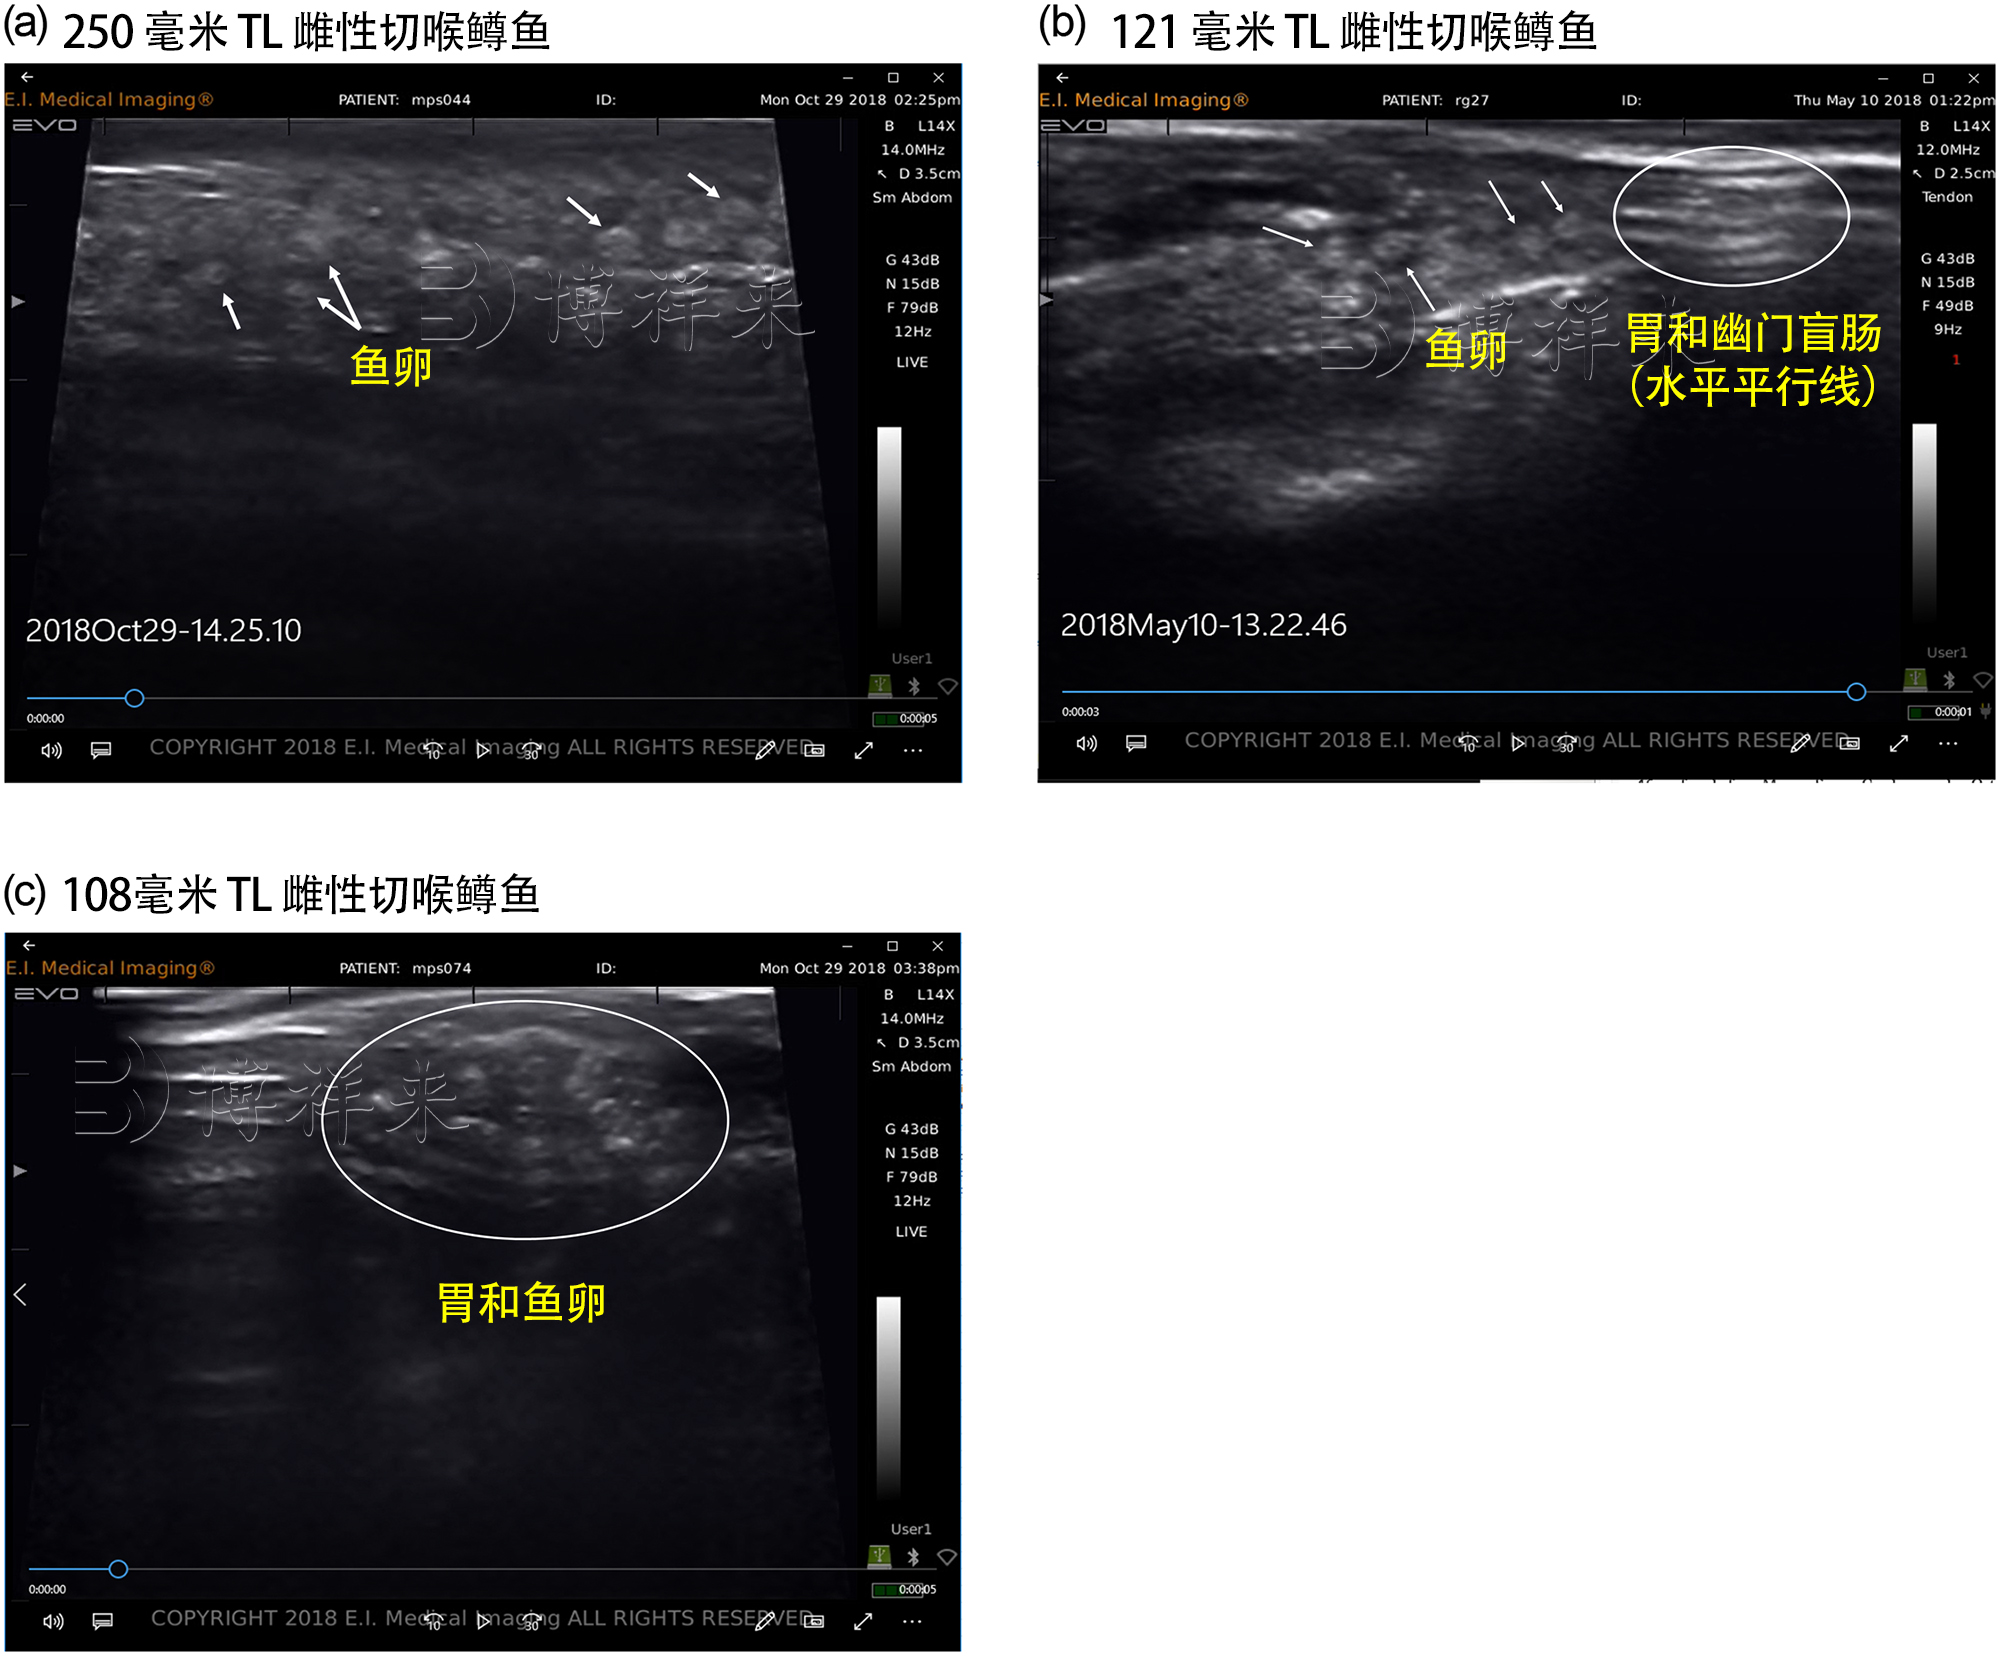

博祥来鱼用B超设备,采用了***的超声波技术,专为水产养殖设计,能够精准监测鱼卵的发育状况,并实时反馈养殖信息。我们的水产专用B超设备通过40MHz高频探头技术,提供0.1mm级别的分辨率成像,大大提高了鱼卵发育监测的准确性。相比传统人工检测和普通B超设备,博祥来B超设备能够提供更快、更精确、更安全的解决方案。

非侵入式检测:博祥来鱼用B超采用超声波成像技术,避免了传统方法中的取样过程,不会对鱼卵造成任何破坏,确保高发育成功率。

智能发育评估:我们的设备通过***的AI算法,能够自动识别鱼卵的发育阶段,精准判定发育进程,准确率高达99.2%。

高分辨率成像:40MHz超高频探头,提供0.1mm级的成像分辨率,确保每一颗鱼卵的微小变化都能被精准捕捉。